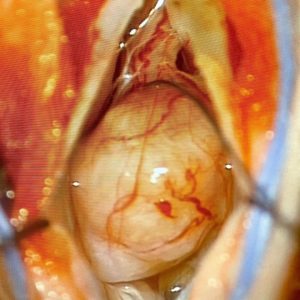

Here is such a case. The patient was very appreciative that we argued with the insurance company to get the MRI of her lumbar spine done. Shortly after the MRI, she began having numbness in her legs in addition to the back pain, and surgery to remove the tumor was necessary.

Knowing about the problem in a timely fashion made all the difference for this patient. Because she was treated early, she made a full recovery and was back to work within a couple of weeks!